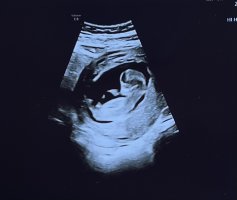

Sikker ?Dette er ei jente. Gratulerer![]()

Det er jo aldri en garanti med ultralydbilder, men ut i fra det jeg kan så er jeg helt sikker i min gjetning om jente i hvert fall!Helt sikker ?

Det er 100% jente. Det der er ikke til å ta feil av.Er 12+3 i dag. Hvilket kjønn tror dere det er ?

Har også dette bilde fra uke 13+0Det er 100% jente. Det der er ikke til å ta feil av.

Ser like jentete ut her!Har også dette bilde fra uke 13+0